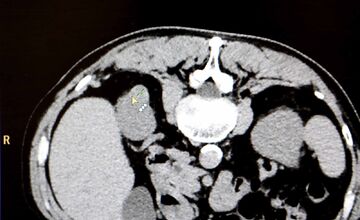

FOTO: Košická univerzitná nemocnica zaviedla pokrokovú liečbu tumorov

VIDEO: Nová nádej pre onkologických pacientov: Unikátna metóda zničí nádor mrazom, využívajú ju aj v Košiciach